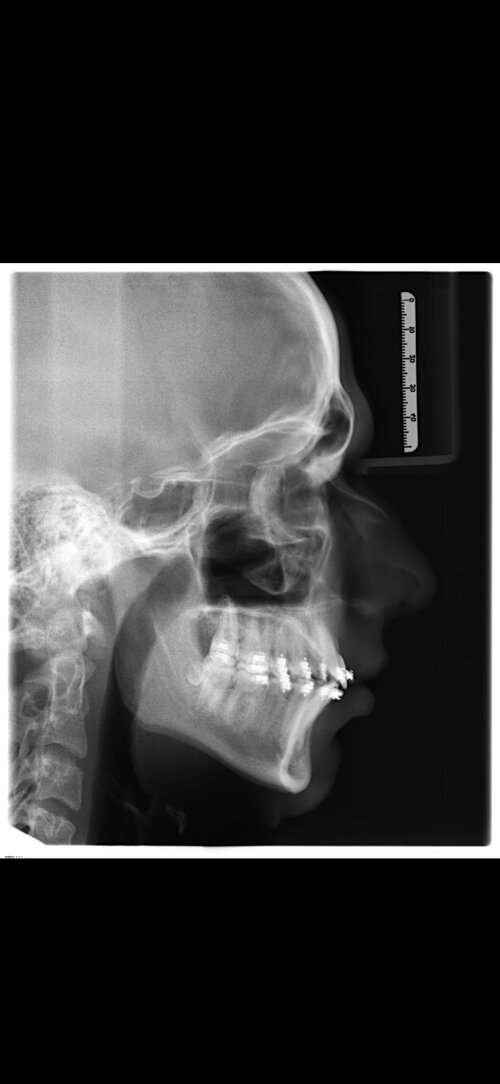

I'm getting bimax surgery performed by a private Jawsurgeon in Germany (Dr Dr Kater, Frankfurt am Main) in 11 days. He's rather doing more conservative movements, but most his patients are people with functional problems at 20 - 30 years. I'm 17 and in a form about the surgery i said 5/5 on aesthetics, mst of his patients say they only want a functional bimax and still get a decent glowup. I'll tell him to "make my chin more masculine and not underprojected), but still Dr Kater isn't one of the big names as far as looks are concerned:

Do yall think i'll still get a big ascension through him or will it be rather underwhelming? I think he'll move both jaws around 5mm, he'll do a very slight CCW Rotation and maybe 6mm sagittal and 2mm vertical movement on the chin.

Pics of my "before surgery base" and an ascension he did on a random girl that wanted functional bimax:

Do yall think i'll still get a big ascension through him or will it be rather underwhelming? I think he'll move both jaws around 5mm, he'll do a very slight CCW Rotation and maybe 6mm sagittal and 2mm vertical movement on the chin.

Pics of my "before surgery base" and an ascension he did on a random girl that wanted functional bimax: